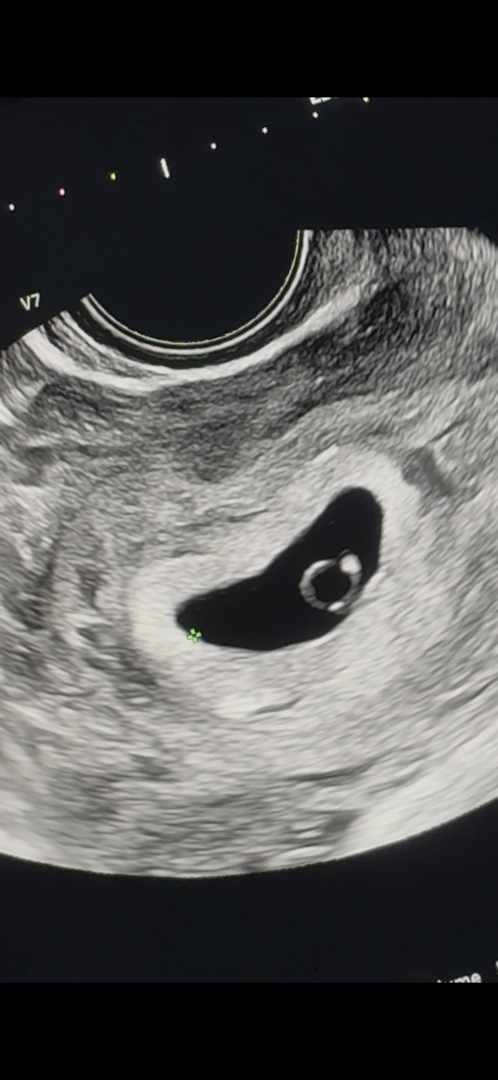

6주 0일차 다이아반지 보고 심소 들었어요ㅠ

지난번 유산 때 심장소리를 못 들어서 긴장하고 병원 다녀왔는게 반지도 보고 심장소리도 들었어요 ㅠ 이제 걱정 좀 덜어낼 수 있을거 같아요

축하드려요~~ 예쁜 반지모양이네요!!

초음파사진이 너무 이쁘게 잘찍혔어요~축하드려용ㅎㅎ